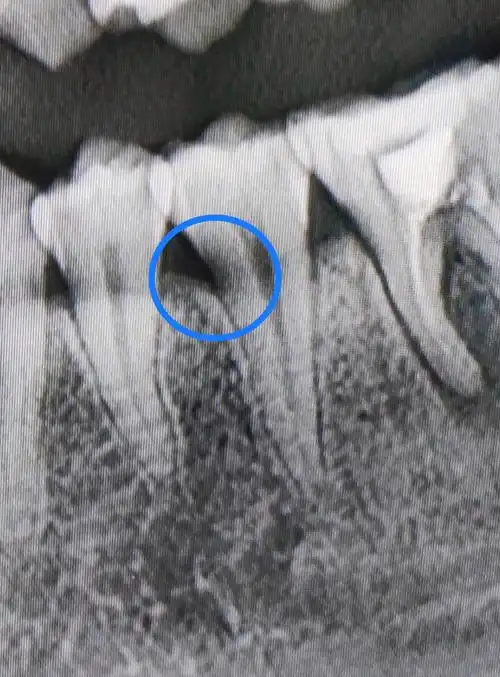

树脂补牙 预成冠 治疗期间发现乳五近中邻面龋

请问这是邻面龋嘛?像这样的,不疼又看不见到底在哪的医生会给补嘛?

乳磨牙的经典坏法---双邻面龋需要每天使.